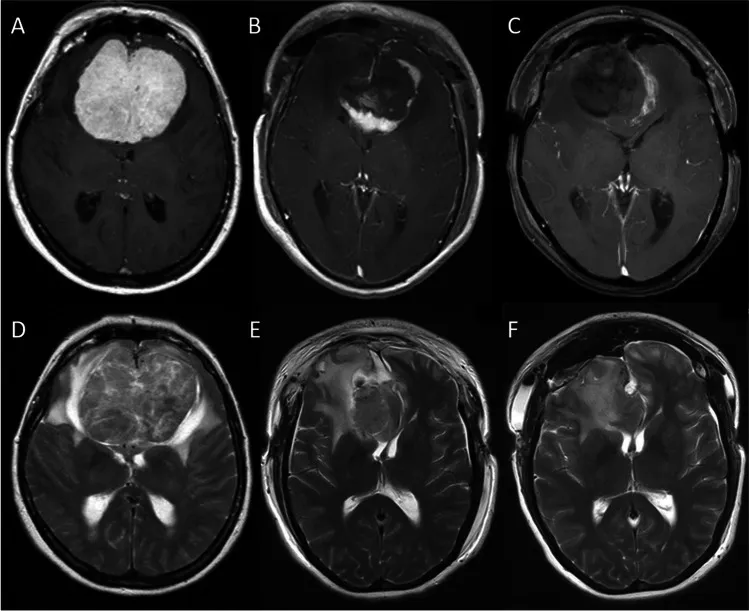

图2:冠状位磁共振成像。增强T1加权(A-C)与T2加权(D-F)图像。A、D:术前图像。B、E:首次术后第一天,显示残留的壳状肿瘤。C、F:第二次术后第一天,显示肿瘤已完全切除。

第一阶段:首先实施双额开颅,继而选择右侧半球间入路。在显微外科技术辅助下切开大脑镰,切除大约80%的肿瘤主体部分,刻意保留一个壳状的肿瘤残腔。此阶段会将视神经显露出来,作为二期手术的重要解剖标志。但肿瘤的侧方边界以及累及大脑前动脉复合体背侧的部分,在此阶段不予分离。

第二阶段:待患者从一期手术中恢复,且脑水肿明显消退之后,进行二期手术。此阶段目标为将残余的肿瘤组织完全切除,并同期完成硬脑膜修补与颅骨成形术。